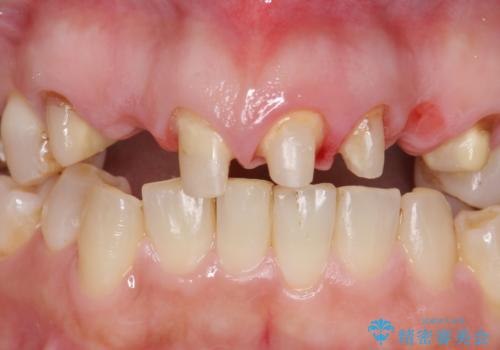

- 昔治療した前歯の被せ物の見た目を改善したいといらっしゃった方の症例です。

左上4番目の歯から右上3番目の歯まで計7歯のクラウンを除去し、オールセラミッククラウンによる補綴を行いました。

- オールセラミッククラウン…¥100,000×7、仮歯…¥10,000×7、ファイバーコア…¥20,000×5費用は治療当時の料金となります